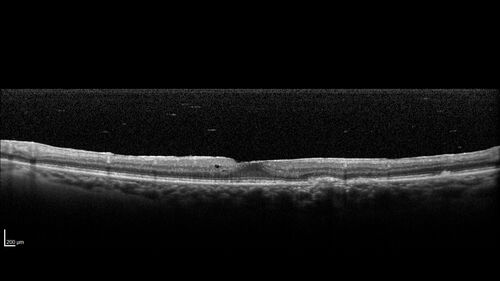

Birdshot Chorioretinitis - Chronic Untreated with Drusen Like Material in Macula

72 year old female with vision changes for years just now diagnosed with Birdshot.